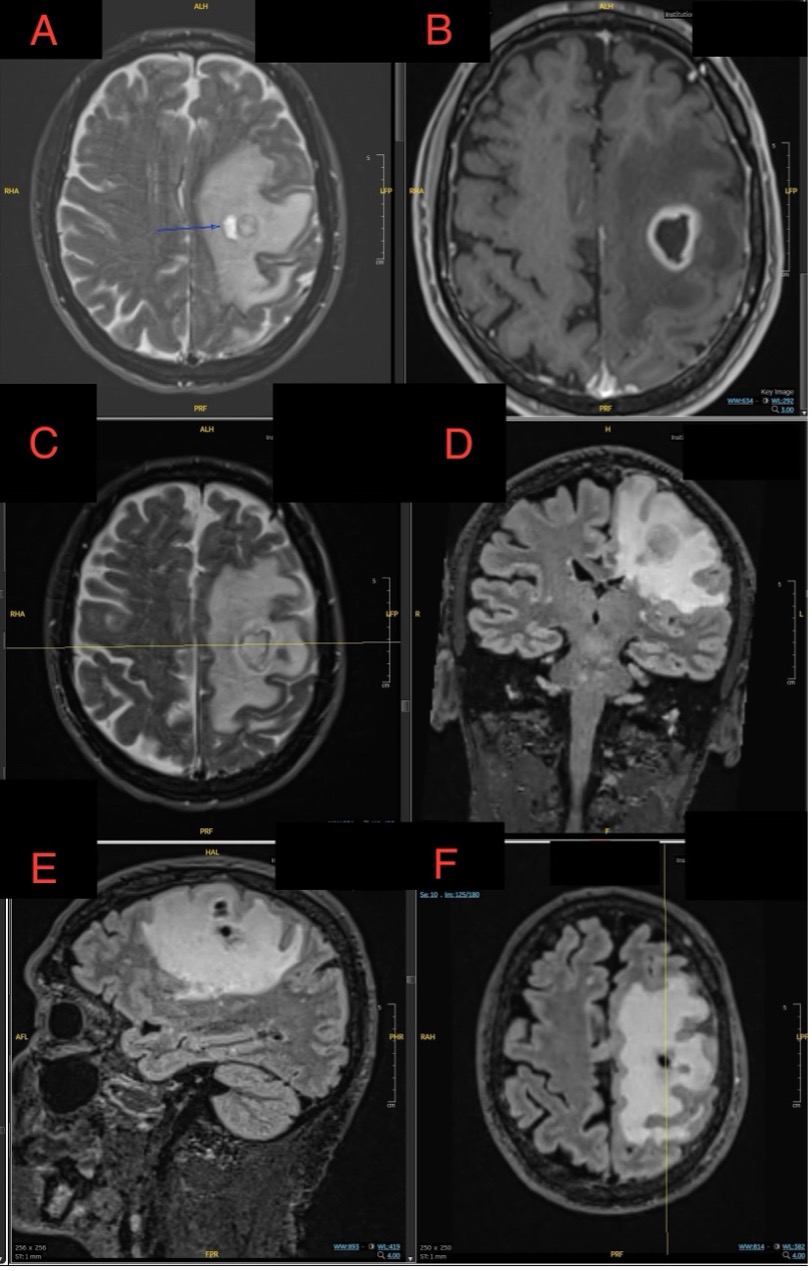

Case Presentation: A 73-year-old male with hypertension, hyperlipidemia, and mild COPD presented with word-finding difficulties. Initial brain imaging at an outside hospital suggested a left intra-axial peri-Rolandic lesion, raising suspicion for a primary brain tumor like glioma. He was transferred for neurosurgical evaluation, where MRI revealed a ring-enhancing lesion with restricted diffusion, consistent with a brain abscess. A stereotactic brain biopsy confirmed a fungal abscess caused by Cladophialophora species.Further evaluation with a chest CT scan showed a nodule with a halo sign in the right lung and a ground-glass opacity in the left lung. These findings were concerning for fungal dissemination but had resolved by the time of the brain abscess diagnosis, making the relationship to the brain infection uncertain. The patient was treated with voriconazole, steroids, and levetiracetam for seizure prophylaxis. He demonstrated significant neurological improvement, regaining strength in his right side from 2/5 to near-complete recovery. He was discharged to a skilled nursing facility with plans for follow-up care, including repeat MRI.

Discussion: This case illustrates the diagnostic challenge of distinguishing fungal brain abscesses from primary brain tumors like gliomas based on imaging alone. The initial presentation and radiographic findings mimicked malignancy, underscoring the importance of maintaining a differential diagnosis that includes infectious etiologies, particularly for lesions that present with ring enhancement. Stereotactic biopsy was crucial for establishing the diagnosis, emphasizing its role in cases where imaging alone cannot definitively differentiate between abscess and tumor.The transient pulmonary findings highlight the potential for fungal dissemination from the lungs to the CNS, even without persistent lung lesions, and stress the importance of thorough evaluation for possible entry points in systemic infections. This is particularly relevant for Cladophialophora, known for its neurotropic tendencies and capacity to infect immunocompetent individuals. Treatment with voriconazole, an antifungal with good CNS penetration, proved effective in this case, but outcomes are often poor without early intervention, with reported mortality rates up to 70%.